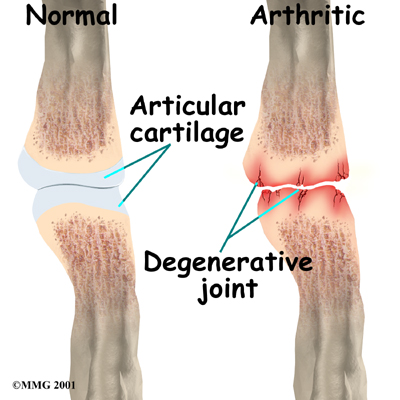

The finger and thumb joints are covered on the ends with . This white, shiny material has a rubbery consistency. The function of articular cartilage is to absorb shock and provide an extremely smooth surface to facilitate motion. There is articular cartilage essentially everywhere that two bony surfaces move against one another, or articulate.

is a condition in which a joint wears out, or degenerates, usually slowly over a period of many years. Degenerative arthritis is usually called osteoarthritis. The term arthritis means joint inflammation (pain, redness, heat, and swelling). The term degenerative arthritis means inflammation of a joint due to wear and tear. You may also hear the term degenerative arthrosis used. Degenerative arthritis is usually called osteoarthritis.

Injury to a joint, such as a bad sprain or fracture, can cause . An injury to any of the joints of the fingers, even if it does not injure the articular cartilage directly, can alter how the joint works. After a fracture, the bone fragments may heal in slightly different positions. This may make the joints line up differently. When an injury changes the way the joint lines up and moves, force can start to press against the surface of the articular cartilage. This is similar to how a machine that is out of balance wears out faster.

Over time, this imbalance in the joint can lead to damage to the articular surface. Since articular cartilage cannot heal itself very well, the damage adds up. Eventually, the joint can no longer compensate for the increasing damage, and symptoms begin. The damage in the joint starts well before the symptoms of arthritis appear.